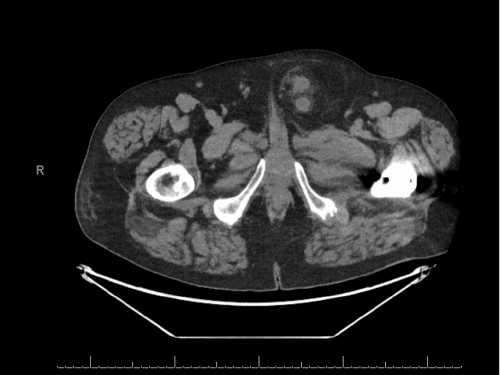

Figure 1. Preoperative CT Imaging of Ureteral Inguinal Hernia. Published with Permission

Coronal view demonstrating severe left-sided hydronephrosis and hydroureter proximal to the point of herniation

Axial view showing the incarcerated and hydronephrotic distal left ureter contained within the left inguinal hernia sac